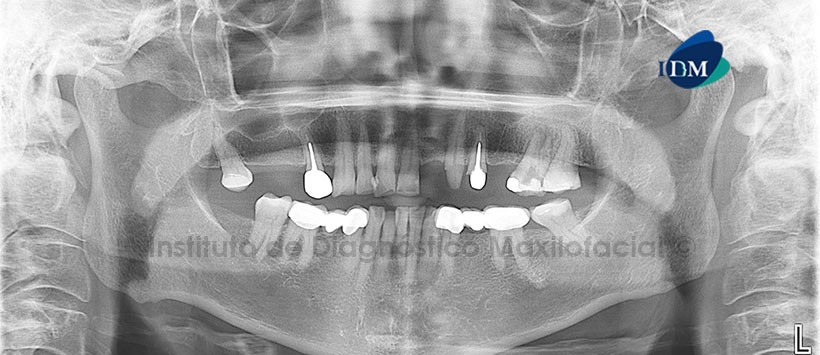

Paciente femenino, 55 años de edad, es referido al Instituto de Diagnóstico Maxilofacial (IDM) para evaluación tomográfica de la pieza 2.6 que se encuentra en tratamiento de conductos y presenta sangrado intracameral.

En la radiografía panorámica (Figura 1) se aprecia neumatización alveolar de senos maxilares, edéntula parcial bimaxilar, piezas con tratamientos de conductos, y tratamiento de prótesis fija. A nivel de la pieza 2.6 se aprecia material de restauración coronal, asociado a procesos osteolítico periapical.